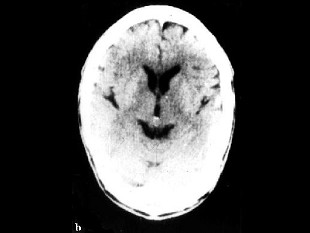

[单选题]男,74岁,突发头疼、意识丧失7小时,行Tc-HMPAO脑血流断层显像如图,最准确地诊断是()A.左侧TIAB.左侧颞叶脑梗死C.左侧顶叶癫痫灶D.右